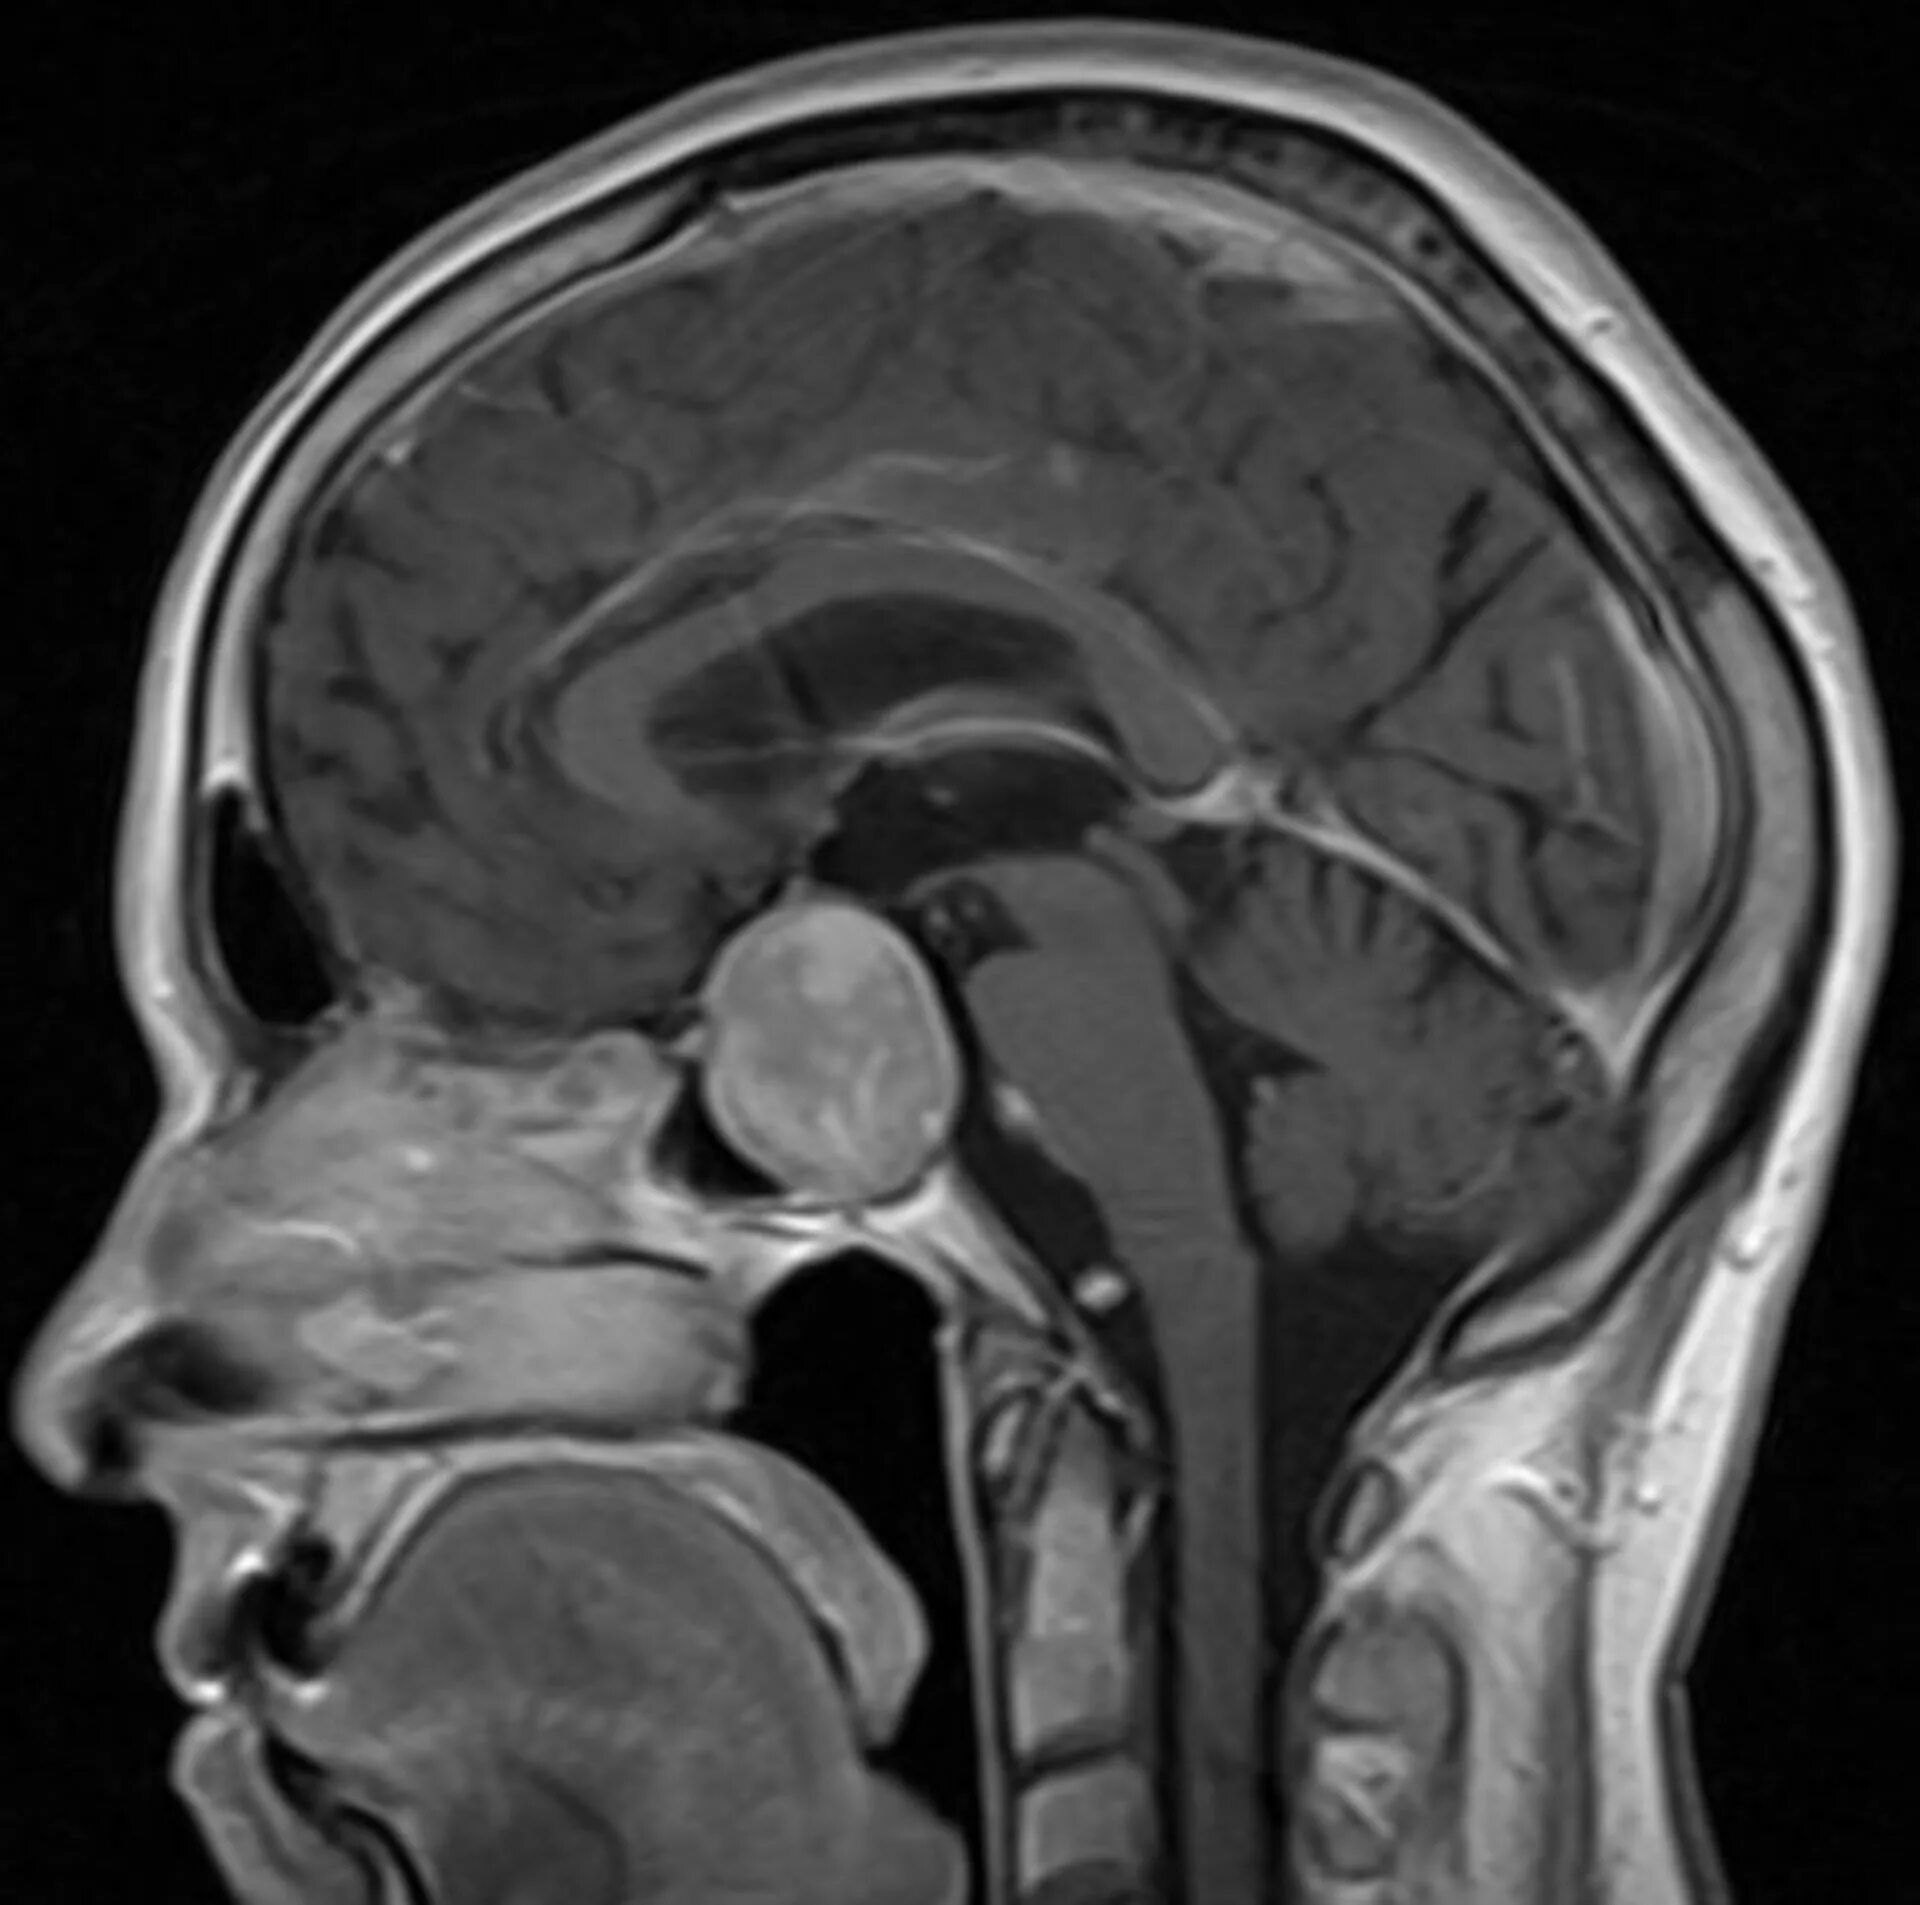

Опухоль гипофиза